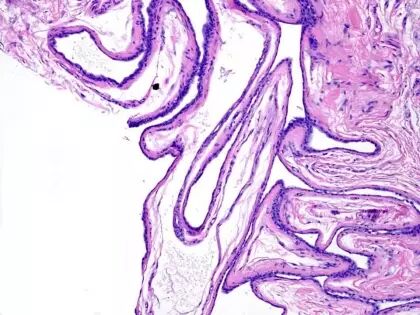

七、乳头状汗管囊腺瘤 (Syringocystadenoma Papilliferum)

病理改变:

1、真皮内数个囊样凹陷,开口皮面, 囊腔上皮与表皮鳞状上皮相连。

2、腺腔内可见绒毛状突起。腔壁及绒毛状突起常由二层细胞组成,内层为高柱状细胞,核卵圆形,胞浆弱嗜酸性,可见断头分泌,外层为小立方细胞,核圆,胞浆少。

3、基质中有大量浆细胞浸润。

4、常可见于皮脂腺痣。